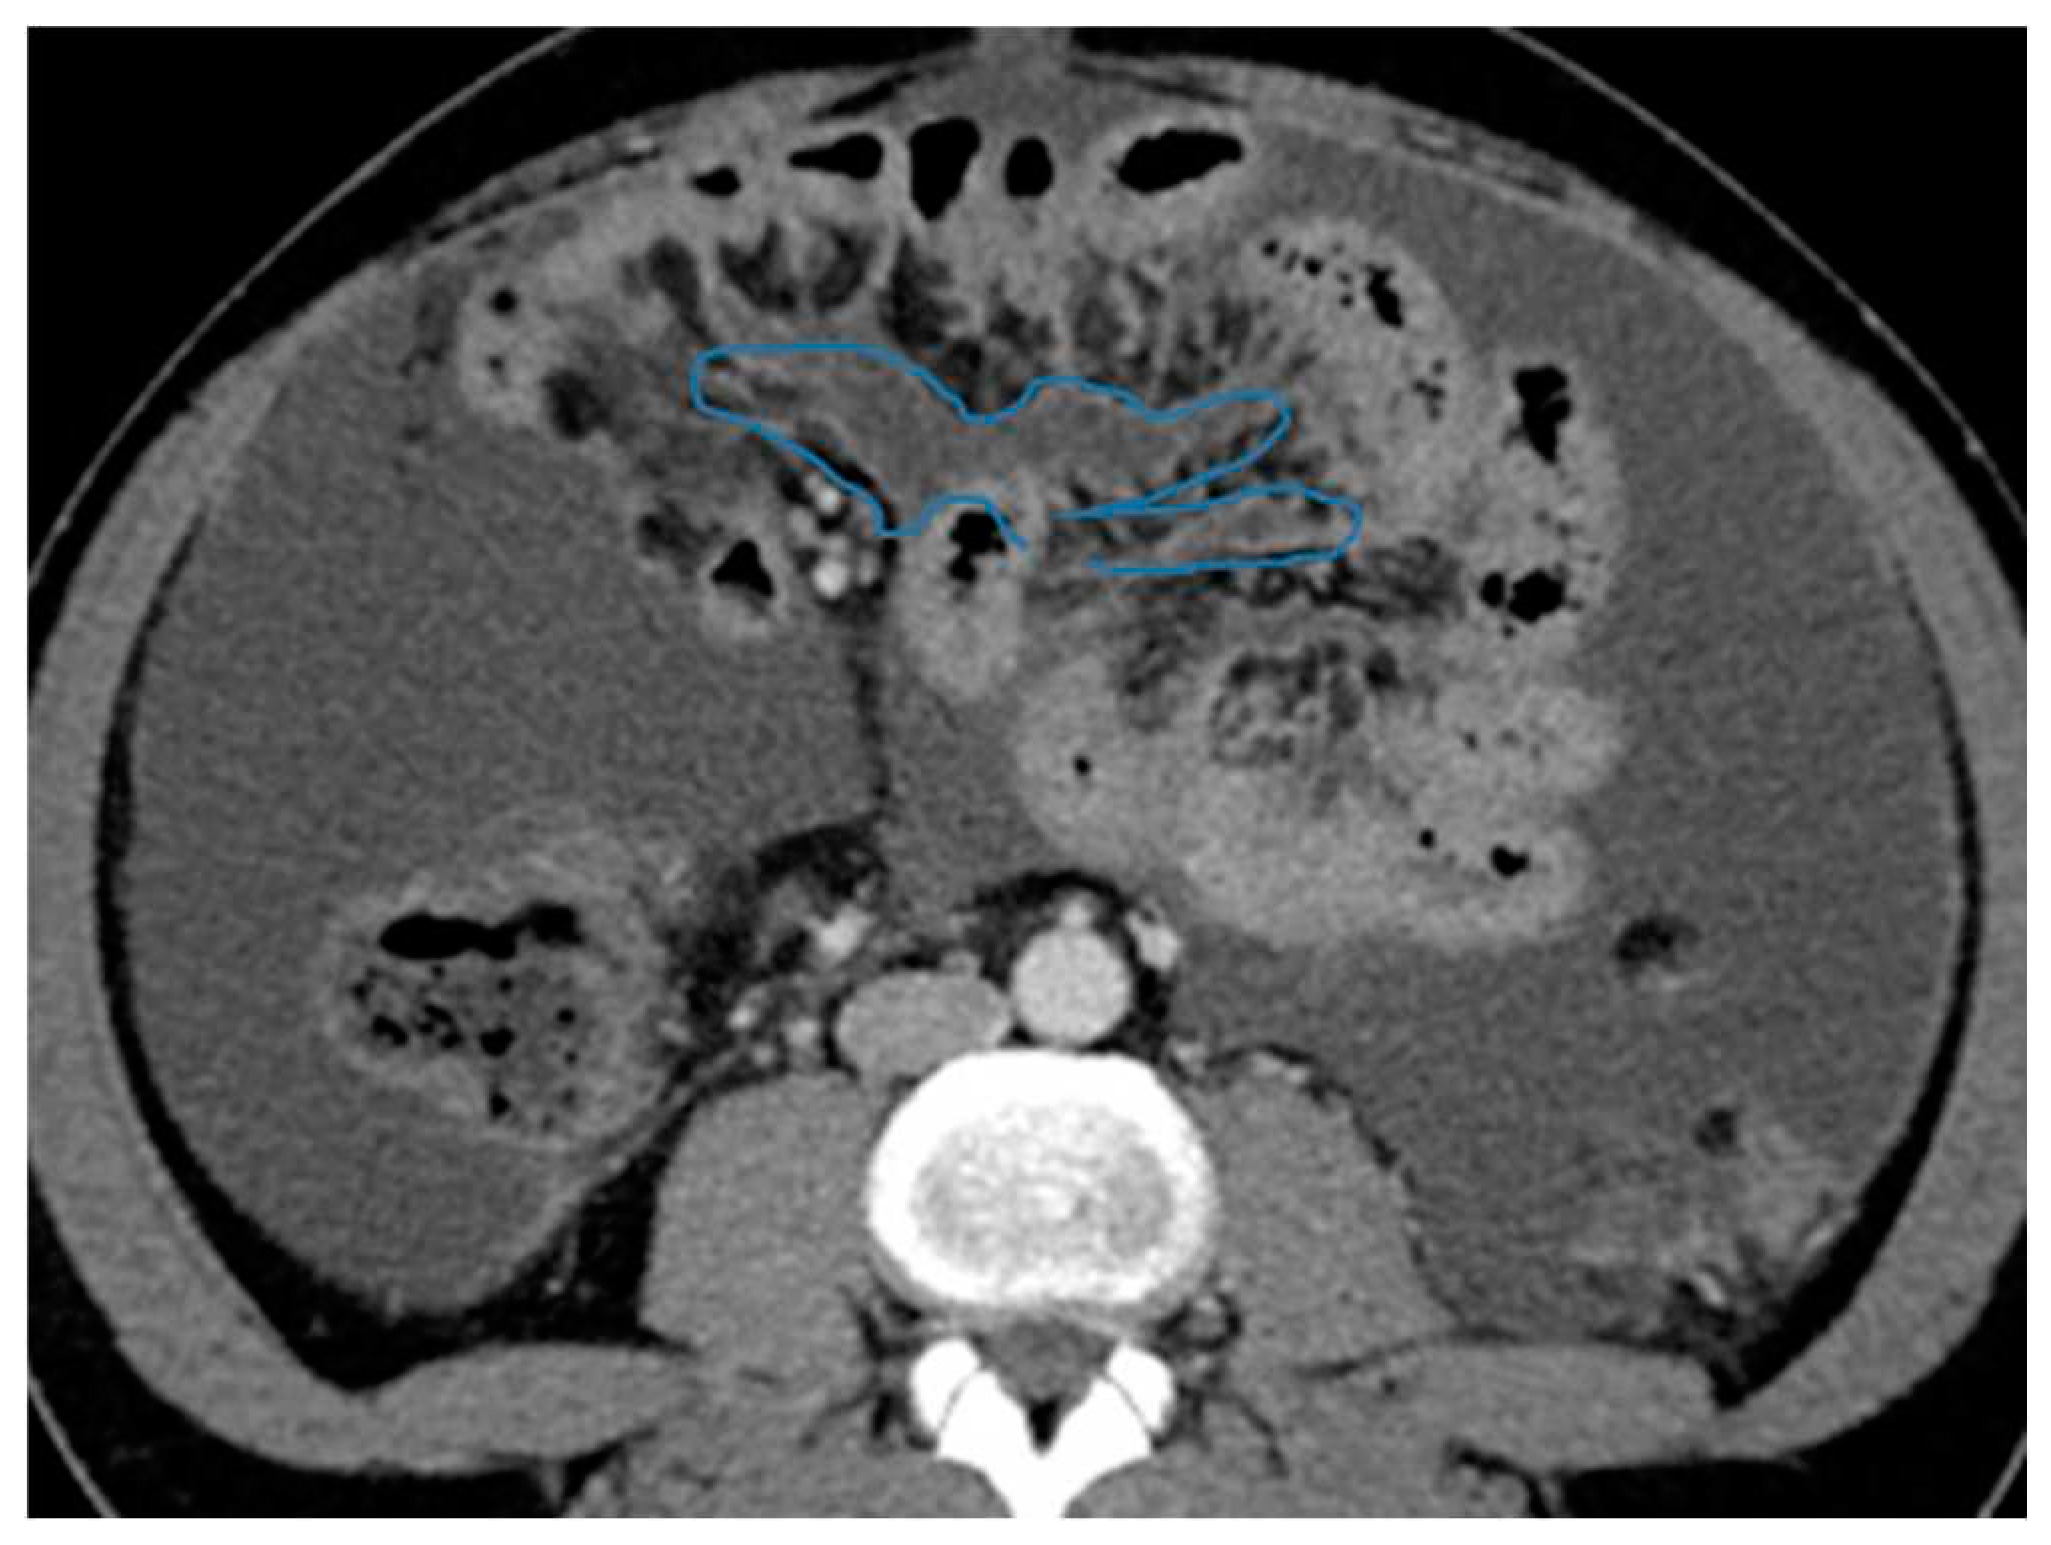

Figure 24.

Axial CE-CT (A), axial T2WI (B), axial CE portal phase FS T1WI (C). PC from endometrial carcinoma: Deposit seeding within the mesenteric leaves.